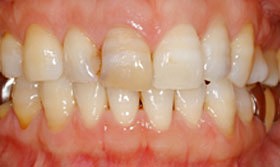

Before

| 主訴 | 歯冠破折 |

| 年齢・性別 | 8歳 男子 |

| 治療期間・回数 | 複数回 |

| 治療方法 | 見えていた歯髄の表層をとり(断髄し)、歯髄の傷が治りやすい薬で傷口を保護しました。その後、折れた破折片を、修復材にてもとの歯に接着しました。 |

| 費用 | 保険適用 |

| デメリット・注意点 | 定期的なレントゲンでのチェックが必要 |